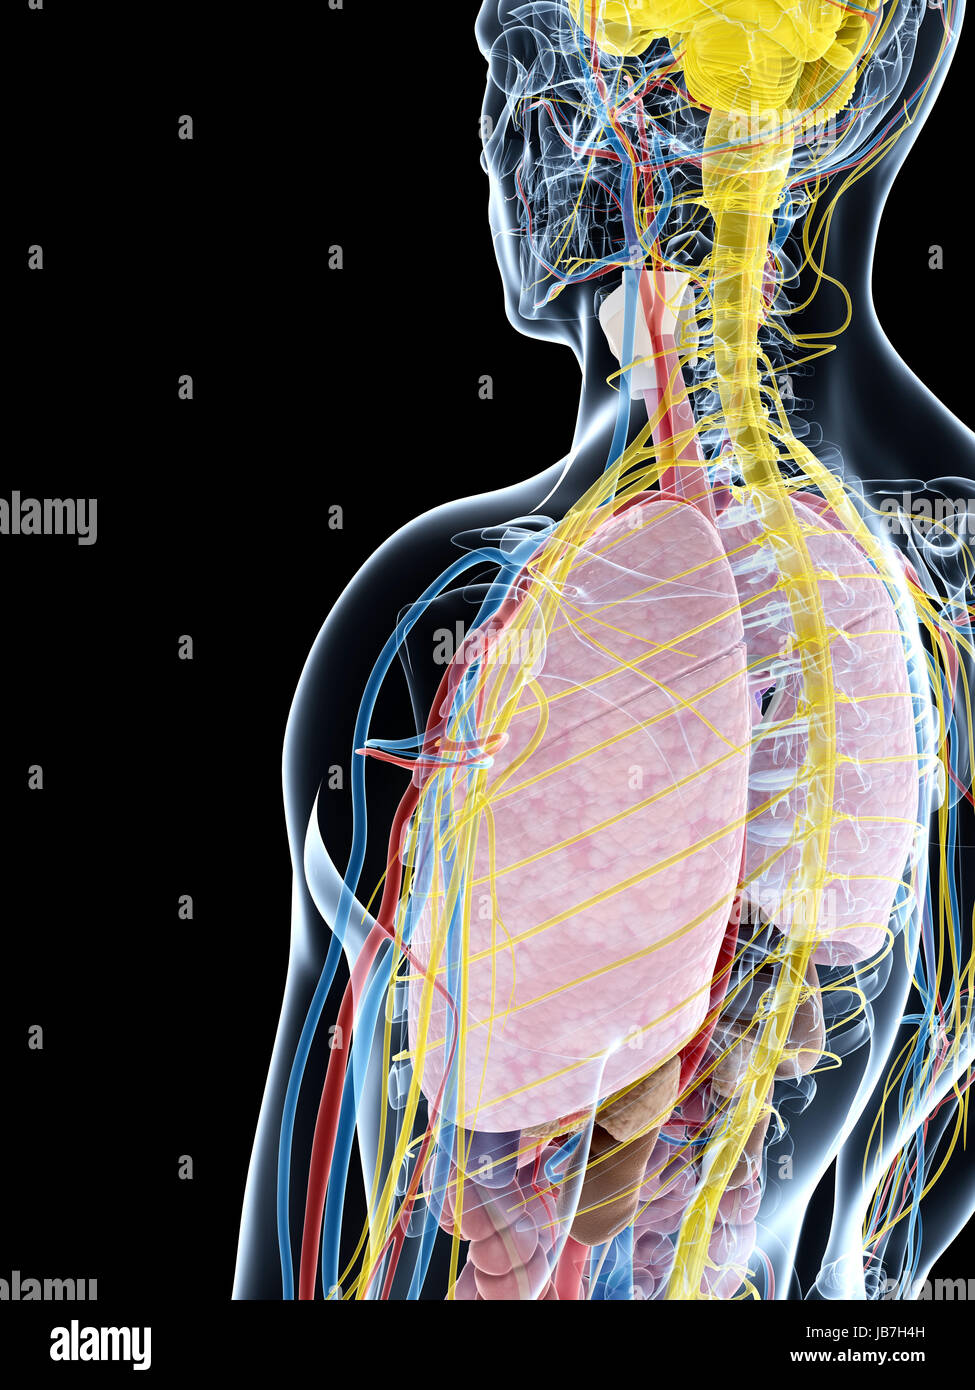

RFDGYRD7–Männliche Anatomie, inneren Organe allein, volle Atmungs- und Verdauungssystem, mit einigen Organen Cutaway. Anatomie-Bild.

RFHT54Y0–Männliche Anatomie. Skelett und hervorgehobenen Lungen. 3D Illustration. Clipping-Pfad enthält.